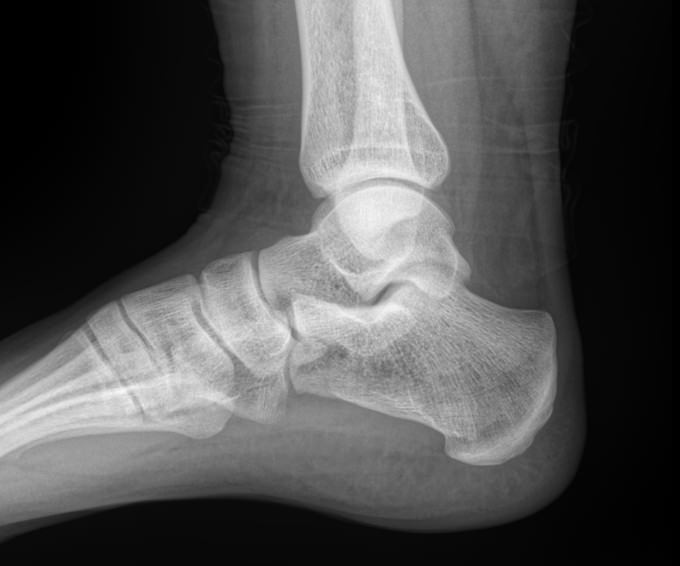

Назад Рентген пяточных костей в боковой проекции

Пяточная кость ― самая крупная среди костей стопы. Нагрузка, приходящаяся на нее, колоссальна. Отсюда и частая травматизация, связанная как со спортом, так и с бытовой и профессиональной деятельностью. Также все патологии, которые развиваются в костной ткани, могут появиться и в пяточной кости. Рентген ― наиболее часто назначаемый вид диагностики при поражении пятки.

На рентгенограмме будут отчетливо видны все структурные изменения, произошедшие с самой пяточной костью и тканями вокруг нее.

Что покажет рентген пяточных костей в боковой проекции

• Целостность кости: переломы, отломки, смещение;

• Состояние костной ткани: разрежение, склерозирование, некроз и другие изменения;

• Конгруэнтность суставных поверхностей и состояние щелей, попавших в область снимка: нормальные, измененные;

• Отечность и инородные тела в мягких тканях пятки;

• Новообразования: опухоли, остеофиты.

Стоит отметить, что остеофиты не являются причиной плантарного фасциита, а вырастают в ответ на хроническое раздражение мягких тканей и свидетельствуют о глубокой стадии заболевания.